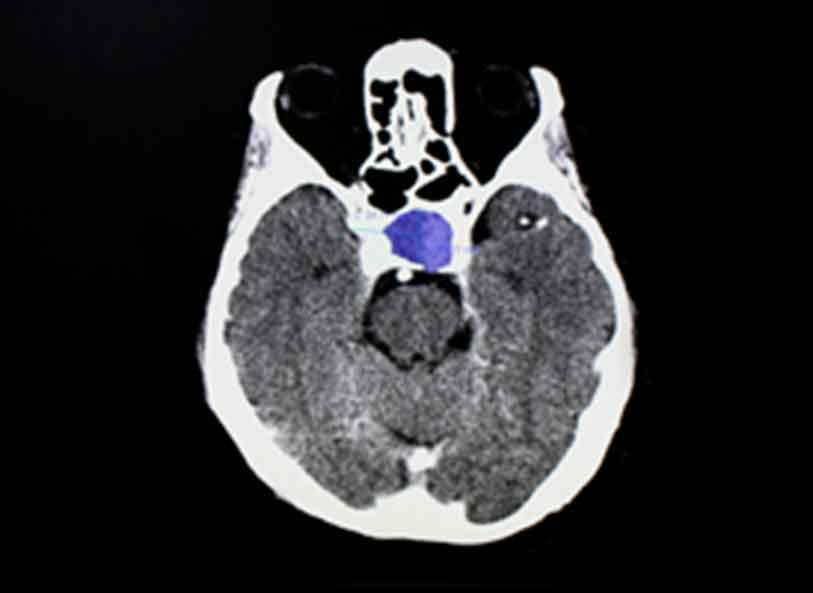

Imaging shows pituitary tumor in brain